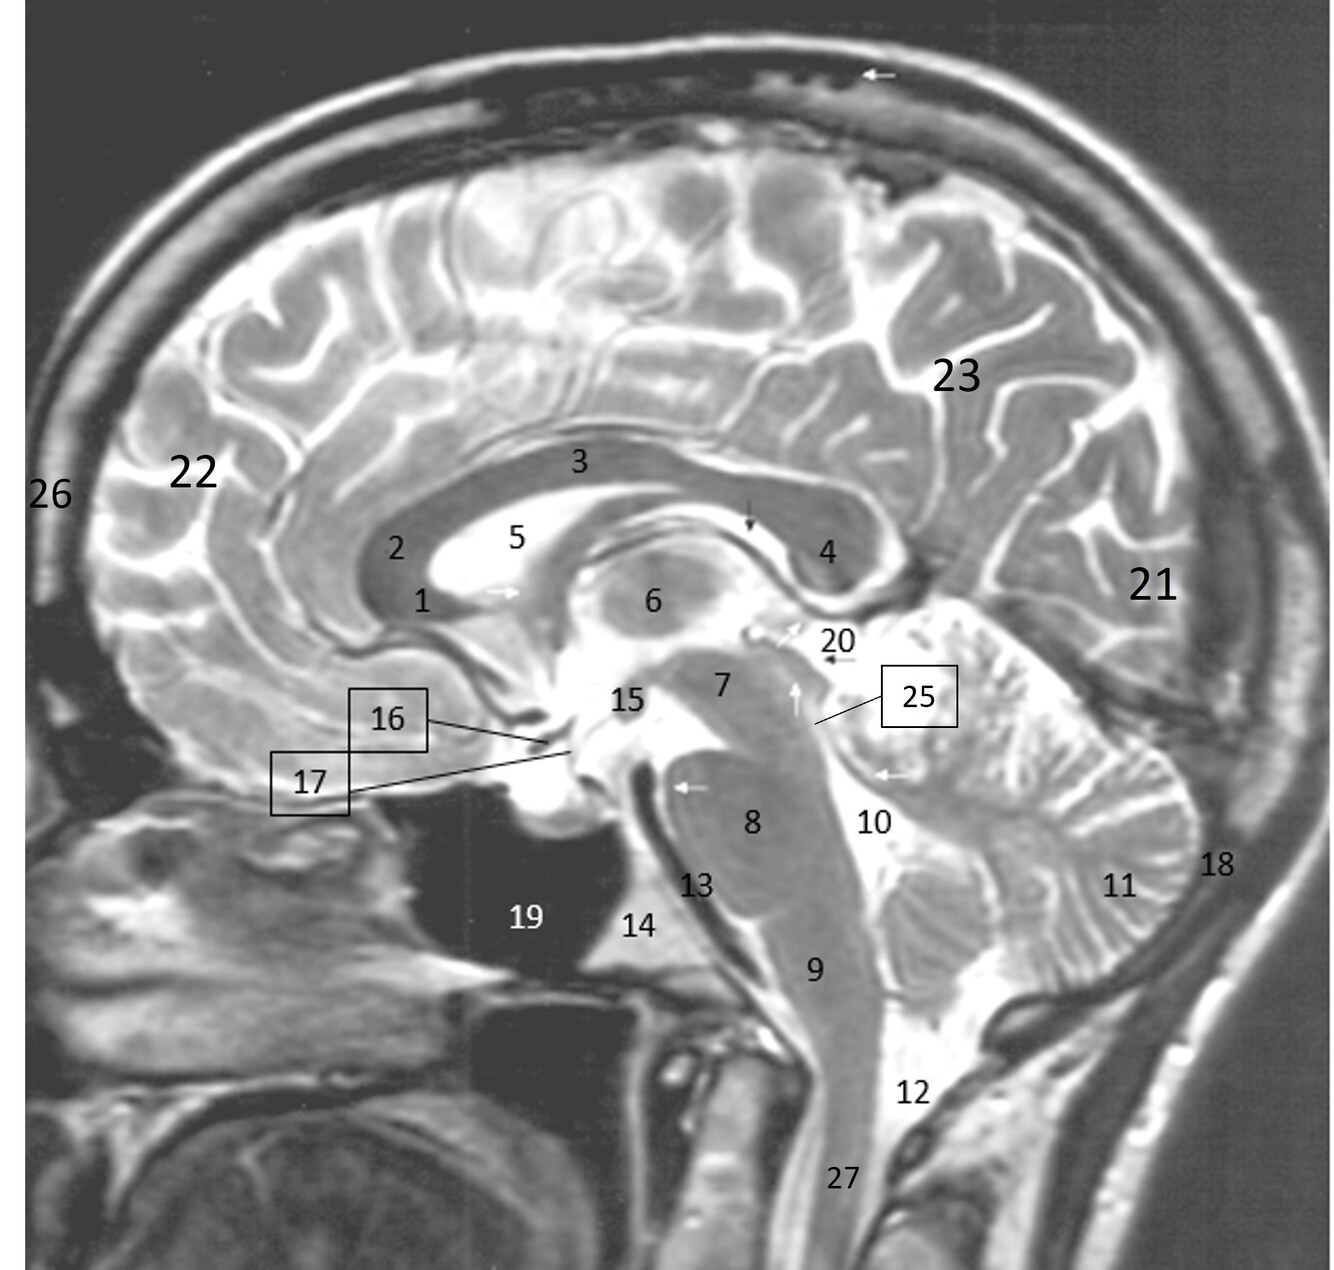

14

Q

Label 1-9

A

1=Rostrum (CC)

2-Genu (CC)

3-Body (CC)

4=Splenium (CC)

5=Lateral ventricle

6=Thalamus

7=Midbrain

8=Pons

9-Medulla oblongata

15

Label 10-18

10-4th ventricle

11=Cerebellum

12=Cisterna Magna

13=Basilar artery

14=Clivus

15-Mamillary body

16=Optic chiasm

17=Infundibulum

18=Occipital bone

16

Label 19-27

19=Sphenoid sinus

20=Quadrigeminal cistern

21=Occipital lobe

22-Frontal lobe

23-Parietal lobe

25-Cerebral aqueduct

26-Frontal bone

27-Spinal canal